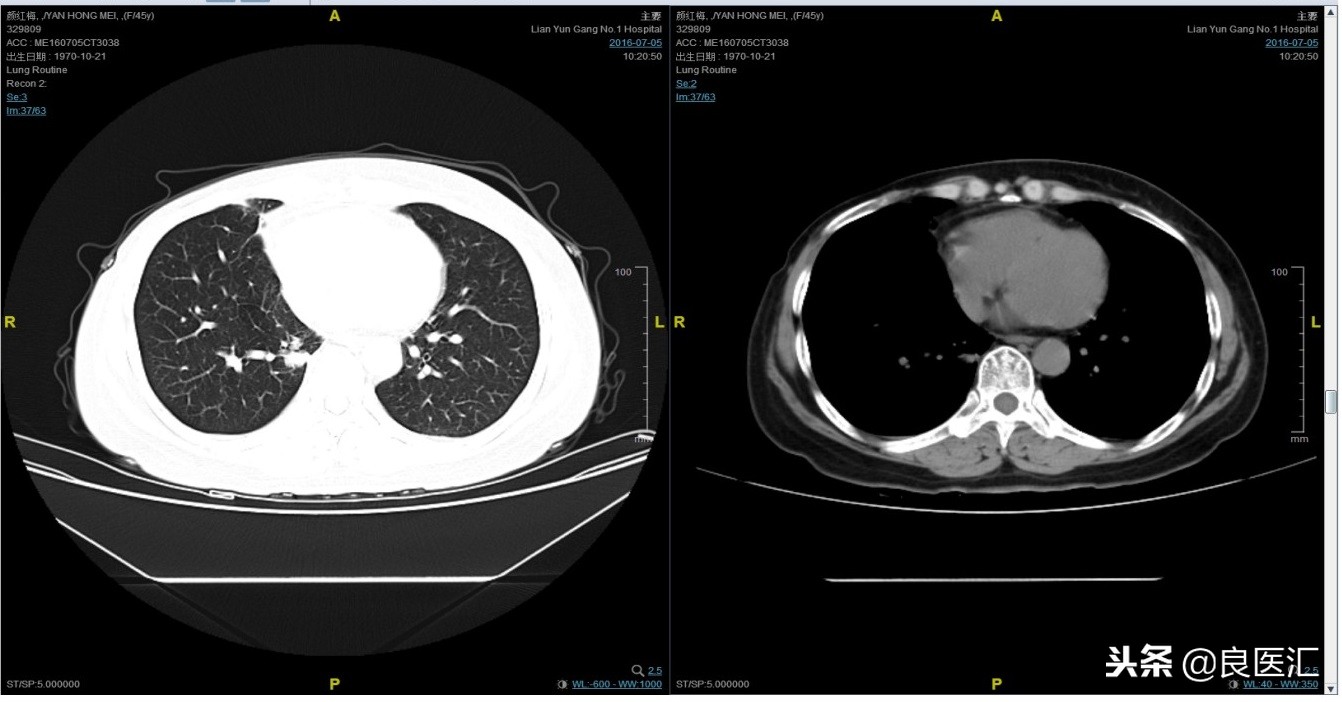

2016-7-5化疗结束后复查CT,疗效评价稳定。